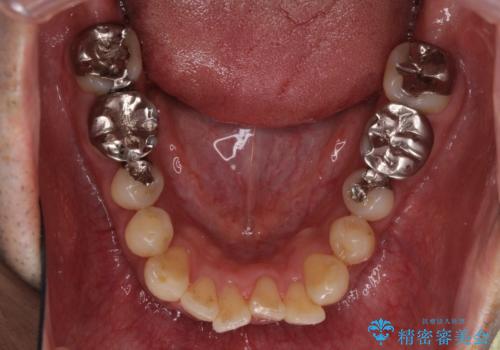

- 隠れるほどに内側に転位しいてる前歯を気にして来院された患者様です。

矯正治療後は、前歯や下顎の奥歯など、むし歯治療途中の歯をオールセラミッククラウンにて補綴治療を行うこととしました。